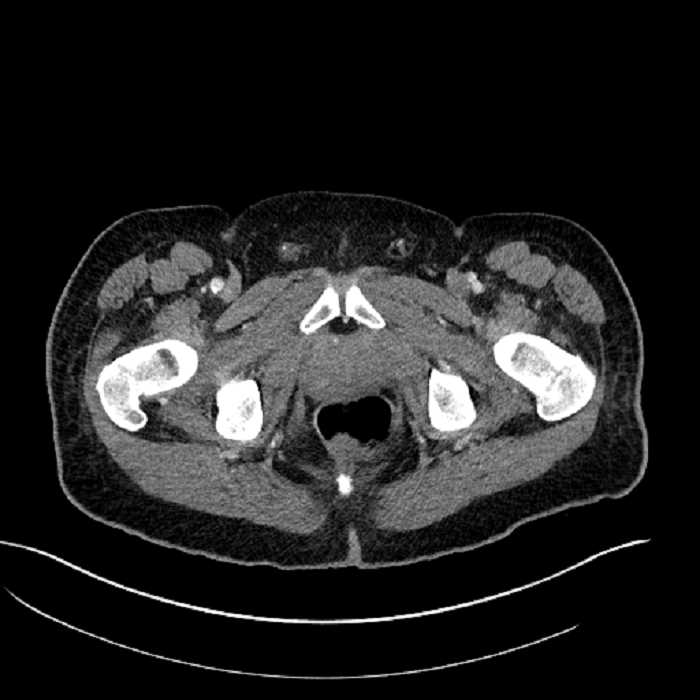

Age: 63

Sex: Male

Indication: Abdominal pain

• Mild mural thickening of a segment of the sigmoid colon with adjacent fat stranding and a 1.5 cm fluid and gas collection along the tip of an inflamed diverticulum

• Loss of the normal fat plane between this collection and adjacent loops of small bowel, which demonstrate mural thickening

• High grade stenosis of the left common iliac artery, with the left internal and external iliac arteries remaining patent

• Ankylosis of both sacroiliac joints

Acute sigmoid diverticulitis complicated by a small contained perforation and a large abscess in the right hepatic lobe. Additional small subcapsular abscesses along the anterior margin of the left hepatic lobe.

Additionally, loss of the normal fat plane between the peridiverticular collection and adjacent thickened loops of small bowel raises the potential for an enterocolonic fistula.

Hepatic abscess showing the double target sign with low density internally surrounded by a thin inner enhancing rim (red arrow) and ill-defined outer low density rim (yellow arrow). Blue arrow indicates an internal septation. Red arrows: additional smaller subcapsular abscesses. Red arrow: focal contained perforation associated with diverticulitis.